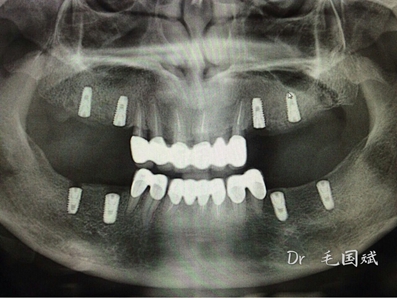

毛國斌種植病例——群討論分享